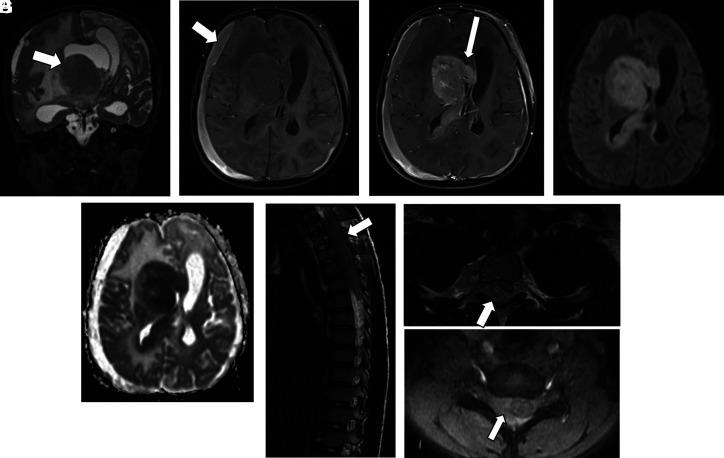

Imaging of Central Nervous System Involvement in Pediatric Hematologic Disorders.

Hematologic disorders and malignancies are commonly encountered in children. The central nervous system is affected by many benign and malignant hematological diseases. Neurologic findings may occur due to central involvement of hematological disease or neurotoxic effects of treatment during the disease. At all these stages, radiological imaging and evaluation have a critical role. In this review article, we aim to describe the imaging findings of central nervous system involvement in pediatric hematologic diseases. This review was prepared based on the latest literature available in the PubMed database in the English language from inception to March 2022. The radiological images of the patients in our archive were obtained from the PACS (Picture Archiving and Communication Systems) to set an example for the diseases described in the text.